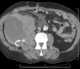

Retroperitoneal hemorrhage

Retroperitoneal bleeding is an accumulation of blood in the retroperitoneal space. Signs and symptoms may include abdominal or upper leg pain, hematuria, and shock. [Source: Wikipedia ]